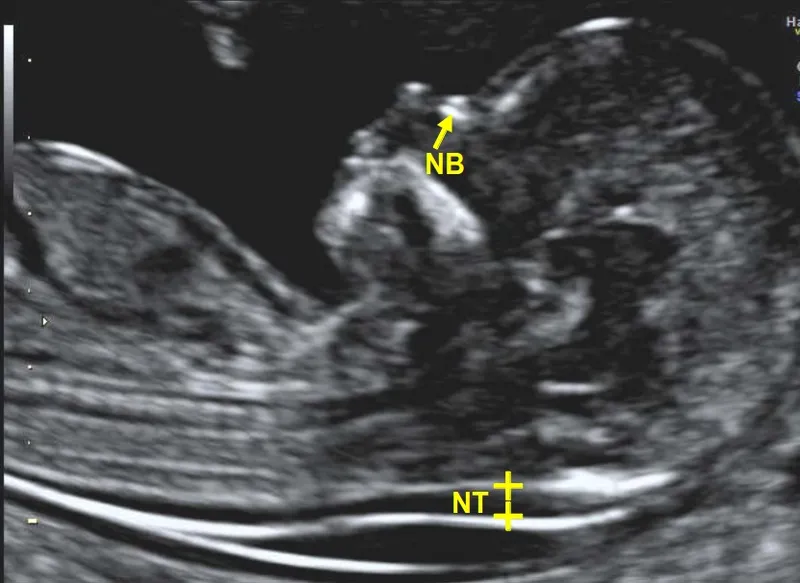

- Ultrasound (USG) Markers:

- Nuchal Translucency (NT): ↑ suggests aneuploidy/cardiac defects. (Normal < 3.5 mm)

- Nasal Bone (NB): Absent ↑ Trisomy 21 risk.